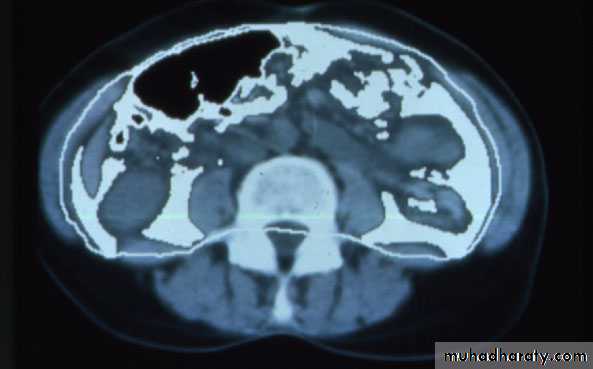

Normal

Visceral AdiposityCourtesy of Wilfred Y. Fujimoto, MD.

Visceral Fat DistributionIDF Waist Circumference